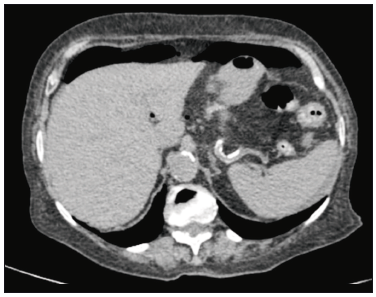

A su ingreso se realizaron estudios, tomografía de abdomen y pelvis, con el hallazgo de hidroneumoperitoneo, líquido libre en la cavidad abdominal, medialización del ciego, marcadamente distendido, con la presencia de un elemento de alta densidad en su interior (¿cuerpo extraño?) (Figura 1-2). Laboratorio: glóbulos blancos 1.8 mill/mm3, creatinina 1.5 mg%, ldh 169 U/l.

Figura 1. TC abdomen y pelvis: hidroneumoperitoneo